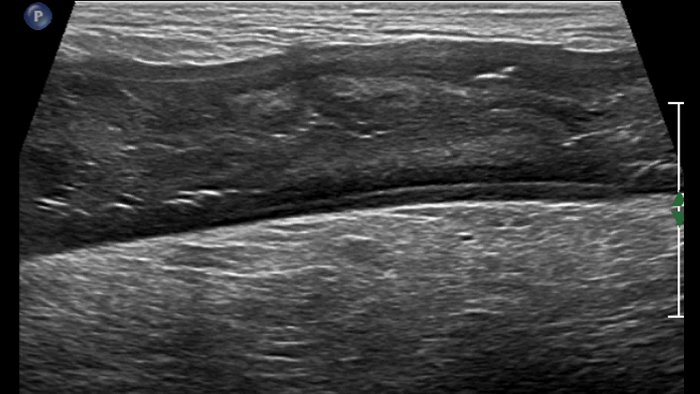

Dans cette présentation, nous exposerons en détail l’intérêt potentiel de la sonde linéaire PureWave eL18-4 pour répondre aux deux premières questions précédemment posées: le diagnostic final de la maladie inflammatoire chronique de l’intestin grâce à l’imagerie haute résolution des changements structurels dans les parois intestinales pathologiques et la recherche de signes d’une inflammation active grâce à la visualisation des microvaisseaux avec le mode d’imagerie MFI. L’imagerie 2D haute résolution est la première étape. Depuis longtemps, l’échoendoscopie nous démontre que l’échostructure des parois intestinales est formée de 5 couches échographiques corrélées aux couches histologiques. De même, une exploration échographique percutanée du tube digestif doit permettre d’identifier les couches intermédiaires entre les couches externes hyperéchogènes qui ne constituent qu’une interface entre la paroi intestinale et la graisse péri-digestive d’un côté et le lumen intestinal de l’autre côté :

Cet aspect est constant dans tout l’intestin grêle et le côlon. Si l’épaisseur pariétale est variable, elle demeure cependant toujours inférieure à 5 mm. La ligne muqueuse peut être linéaire ou ondulée en présence de villosités ou de plis. Par ailleurs, le péristaltisme peut gêner l’identification des couches. La nouvelle sonde eL18-4 offre de manière complémentaire la haute résolution et la cadence d’acquisition requises pour pouvoir visualiser nettement les couches de la paroi intestinale. A titre d’exemple, voici un comparatif de la maladie de Crohn et de la rectocolite hémorragique (même échelle) :

Dans les formes tardives de la maladie de Crohn, la différenciation des couches a tendance à s’estomper avec le développement d’une fibrose transmurale et devient ensuite invisible. La scléro-lipomatose du tissu adipeux mésentérique adjacent est hypertrophique et a un aspect en verre dépoli. Les fistules actives se présentent sous forme de trajets hypoéchogènes linéaires entre la paroi digestive et la scléro-lipomatose.